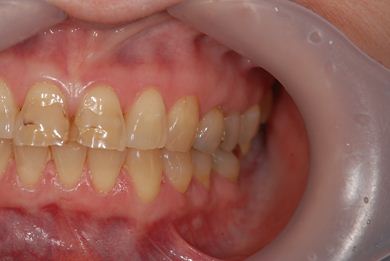

性別/年齢 女性 / 54歳

主訴 抜歯したところのインプラント治療を希望。

治療内容 インプラント1本、メタルボンドセラミック1本

治療前

• 治療前